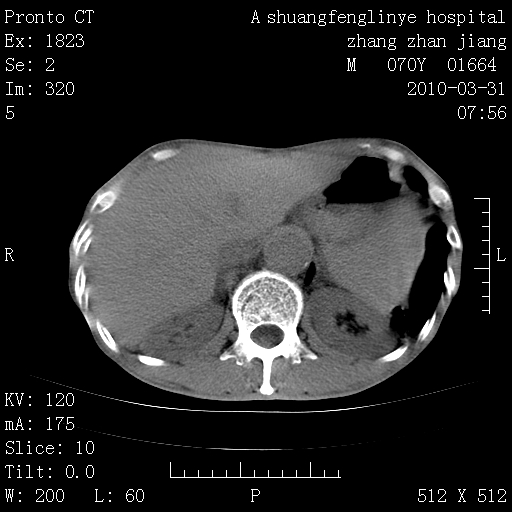

双上肺继发型tb并左上空洞形成,主动脉冠脉钙化。

1)两肺上叶继发性肺结核并左肺上叶空洞形成。2)冠状动脉及主动脉钙化。